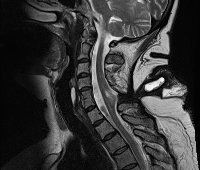

Q04.8 Другие уточненные врожденные аномалии мозга